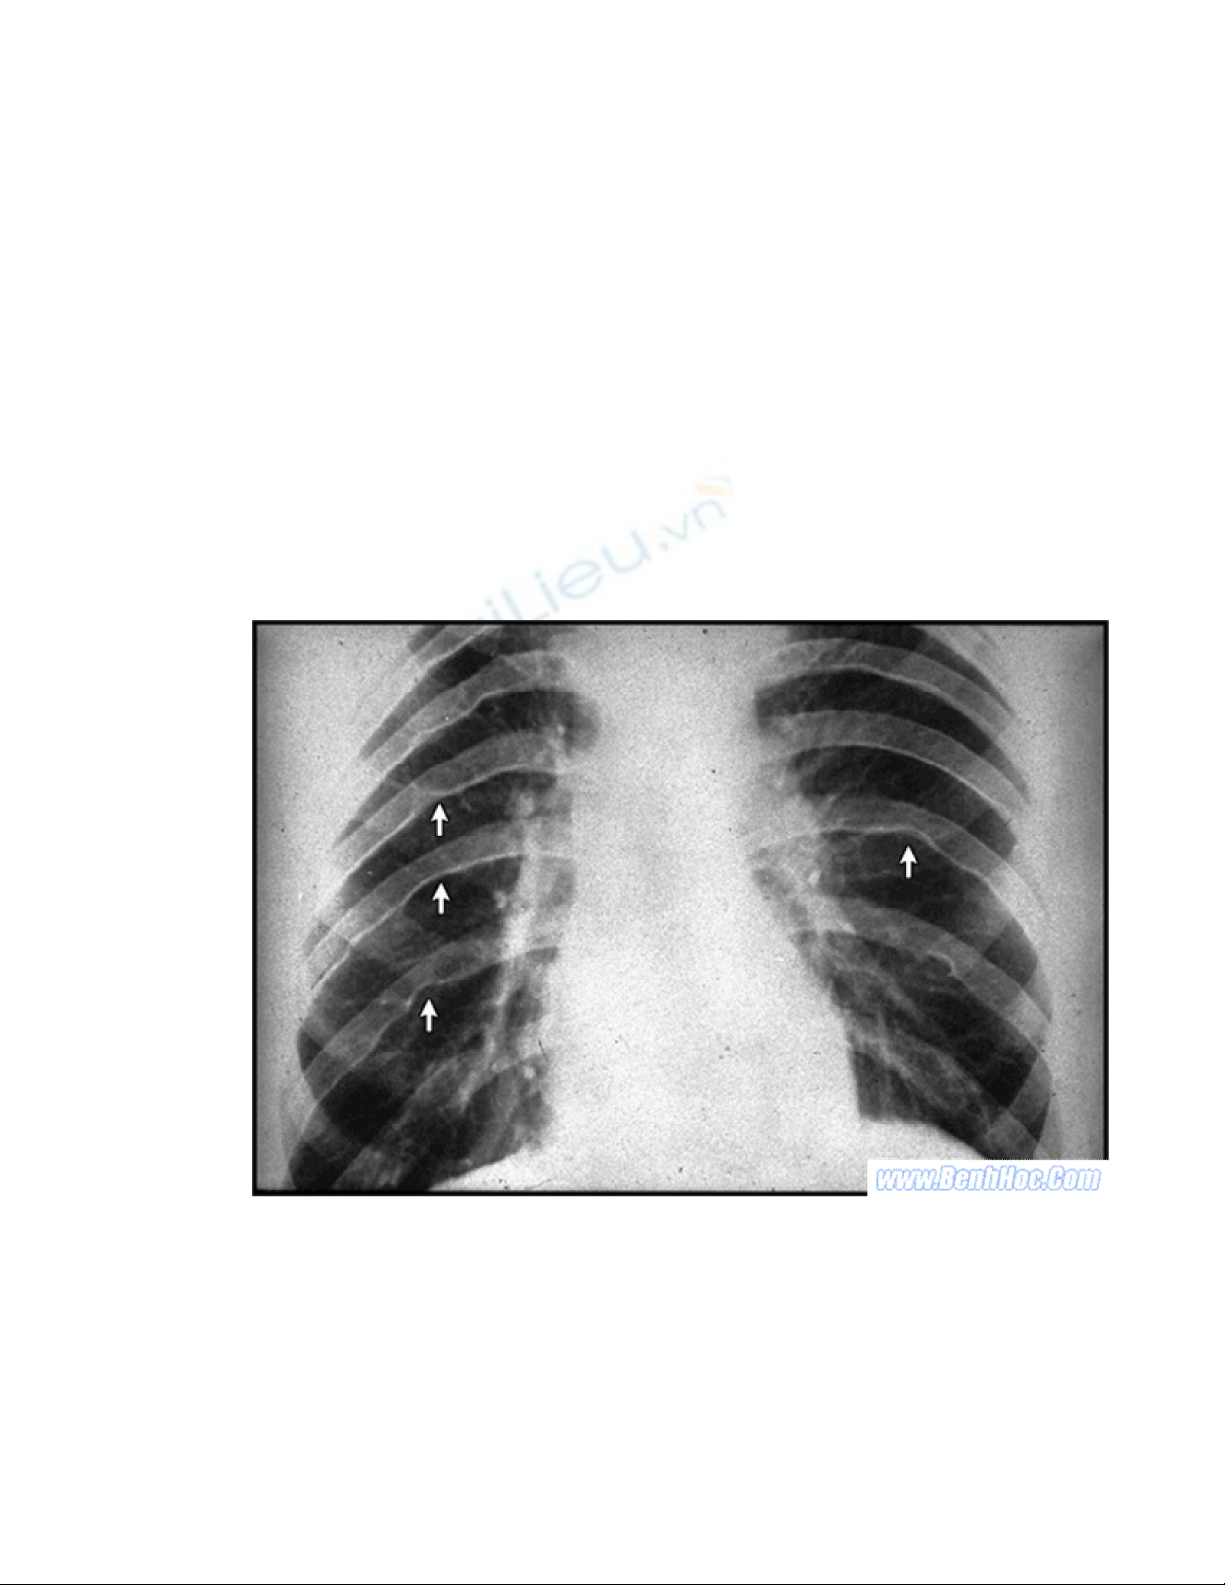

B. Xquang ngực: Có thể bình thờng hay biến đổi nhẹ với cung dới trái

giãn. Kinh điển có thể thấy dấu hiệu 3 cung ở động mạch chủ, quan sát thấy ở t thế

thẳng mặt. Sau vài tuổi có thể thấy các dấu hiệu đặc hiệu hơn nh: dấu ấn xơng sờn,

chỉ số tim ngực tăng rõ rệt.

Hình 32-1. “Dấu ấn sờn” trên phim tim phổi thẳng.